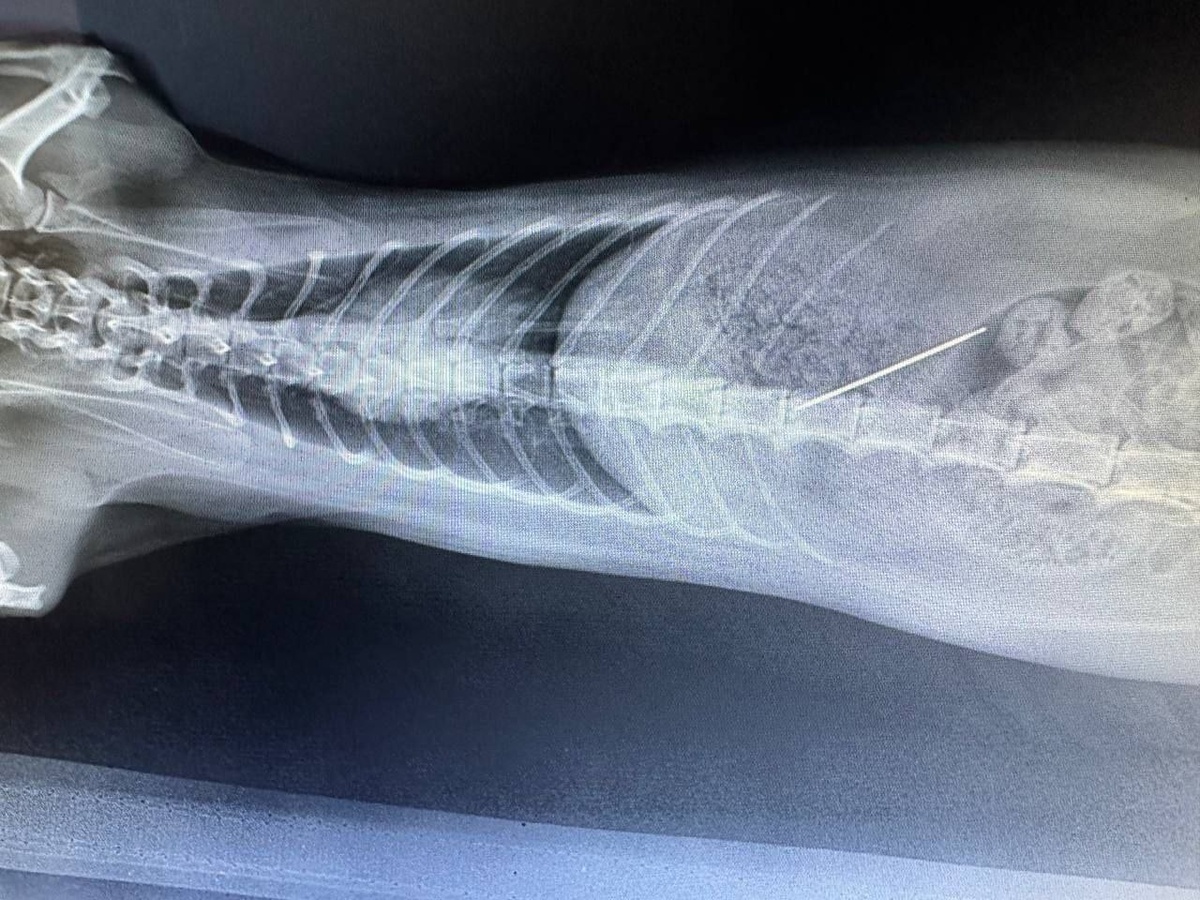

В Севастополе ветеринары спасли кошку, проглотившую иглу

В госветклинику на ул. Могилевская экстренно доставили двухлетнюю кошку Милу, которая проглотила иглу с нитью. Ветеринар Александра Полиновская успешно провела операцию, животному назначили курс антибиотиков, сообщил губернатор Михаил Развожаев.